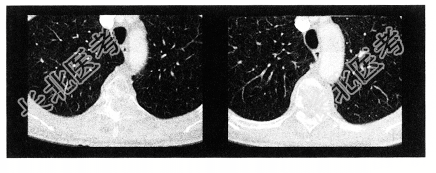

- 单项选择题女性,58岁。背部隐痛2个月余, 1年前行乳癌根治术,结合影像学检查, 最可能的诊断

E、脊柱转移瘤